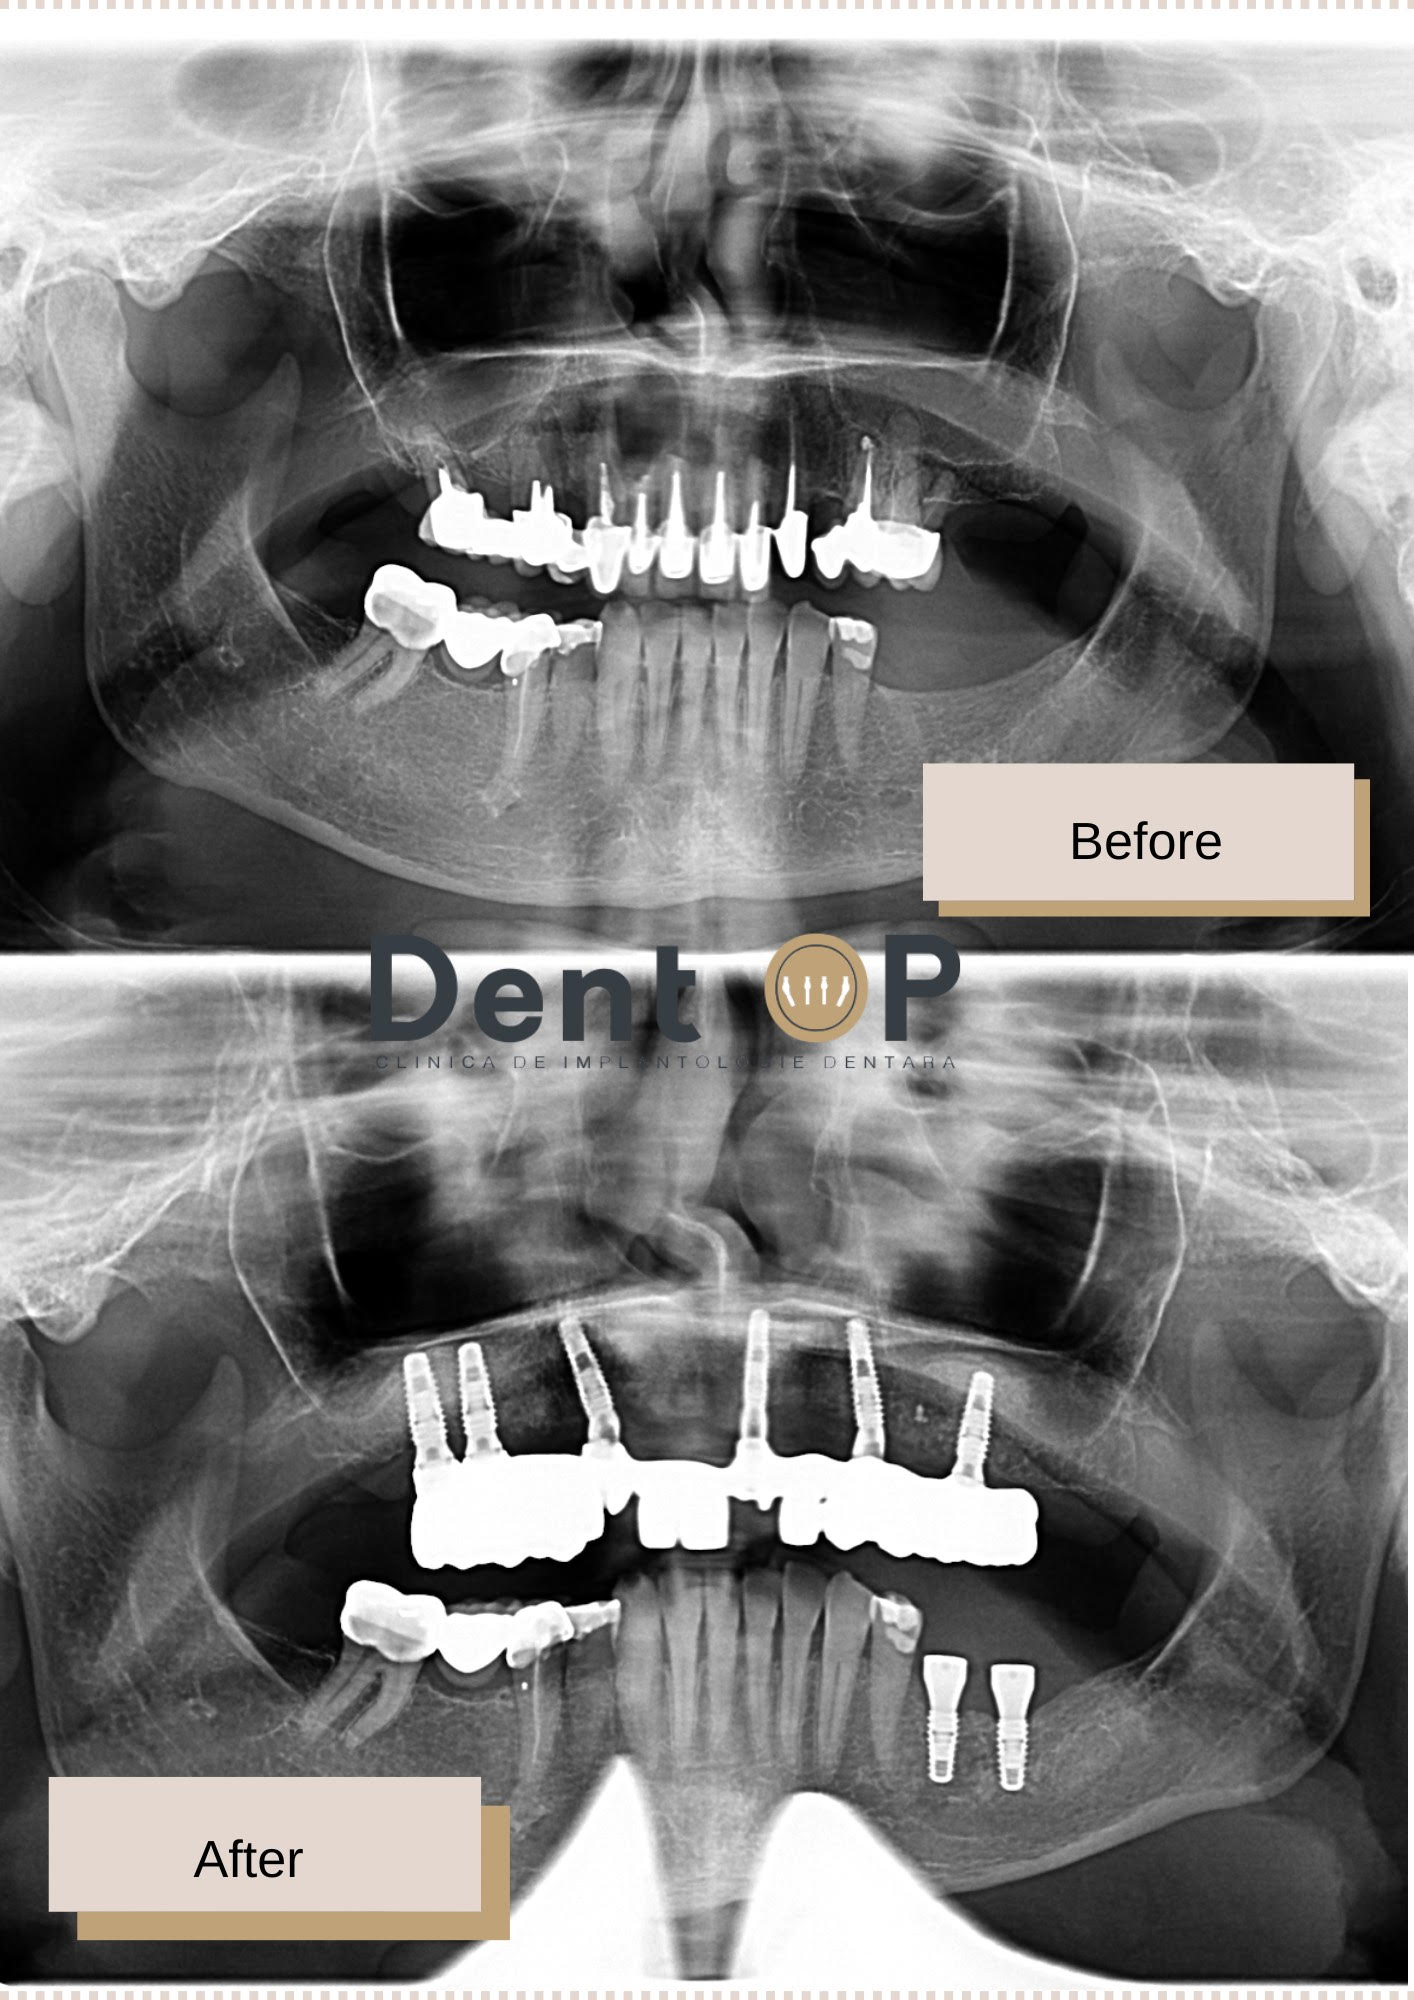

S-a prezentat cu un chist mare la nivel osos și alte afectiuni sub lucrarea cea veche, dar acum zâmbește cu încredere

Se bucură acum de un zâmbet frumos și sigur, dar înainte de intervenția de inserare a celor 6 implanturi dentare, s-a prezentat cu un chist mare la nivelul maxilarului și o lucrare veche, care nu mai era sănătoasă.

Dr Cazacu Corrado – Medic Specialist Chirurgie Dento-Alveolară a observat toate aceste probleme și i-a propus un plan de tratament de reabilitare totală a maxilarului, după îndepărtarea chistului și a lucrărilor vechi.

Doamna I. , deși speriată la început, a acceptat planul de tratament și a avut curajul să aleagă procedura ,,Dantură Fixă în 24h pe implanturi dentare”. Într-o singură ședință posibilă cu ajutorul Sedării Conștiente, i-au fost inserate 6 implanturi dentare. Nu a simțit nici durere și nici frică, iar Medicul ATI a supravegheat în permanență intervenția sa.